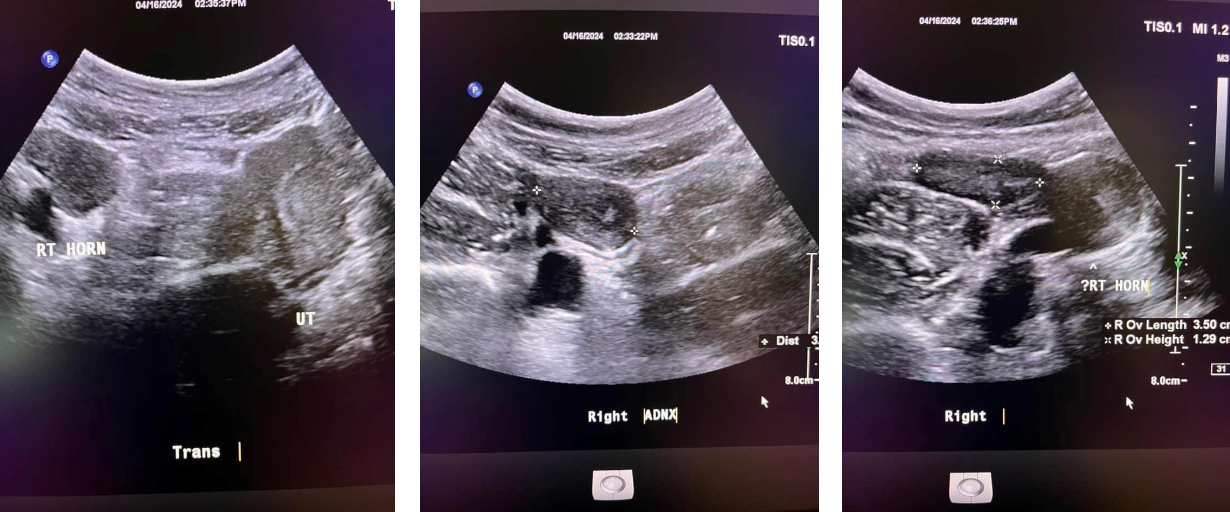

What is the Differentail Consideration for the Uterus for ENLARGES UTERUS?

➢ Bicornuate or didelphic uterus

– Double vaginas, cervixes, and uteri function separately

– The two uteri are at approximately a 450 angle to one another

Uterus Didelphus

– Improper fusion leads to two partially or completely separate bicornuate uterine cavities.

– The uterus is heart-shaped

– Most common congenital uterine anomaly.

Bicornuate uterus